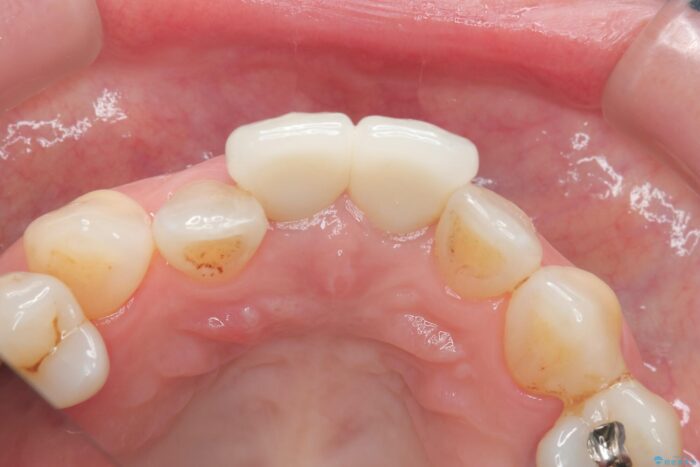

審美性に優れるジルコニアクラウンによる治療を計画します。

黒ずみもなくなり、自然な色味で大変ご満足いただけました。